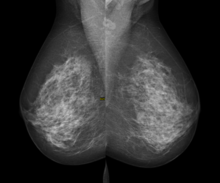

Digital mammography

Digital mammography is a specialized form of mammography that uses digital receptors and computers instead of x-ray film to help examine breast tissue for breast cancer.[1] The electrical signals can be read on computer screens, permitting more manipulation of images to theoretically allow radiologists to more clearly view the results.[1][2] Digital mammography may be "spot view", for breast biopsy,[3] or "full field" (FFDM) for screening.[1]

While radiologists[4] had hoped for more marked improvement, the effectiveness of digital mammography was found comparable to traditional x-ray methods in 2004, though there may be reduced radiation with the technique and it may lead to fewer retests.[1] Specifically, it performs no better than film for post-menopausal women, who represent more than three-quarters of women with breast cancer.[5]